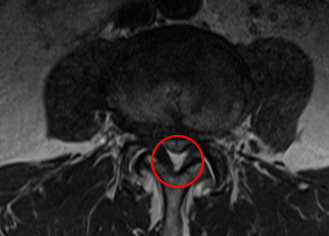

手術の翌日には、座っていると少し痛みが出るものの、これまであった左足の痛みはなくなったそうです。さらに術後1か月目には腰痛は10から2に、足の痛みは10から0になりました。術後の腰椎MRIでもL4/5が減圧していることを確認しました。さらに術後2か月目は、腰痛の痛み指数も0になりました。

治療では、痛みの原因だと考えられるL4/5の狭窄を取り除く手術「PEL」を局所麻酔下のもとで実施し、神経の圧迫を取り除きました。最後には、神経細胞の修復作用効果と、患部の修復促進効果を期待して、再生医療「PRP療法」を施しました。